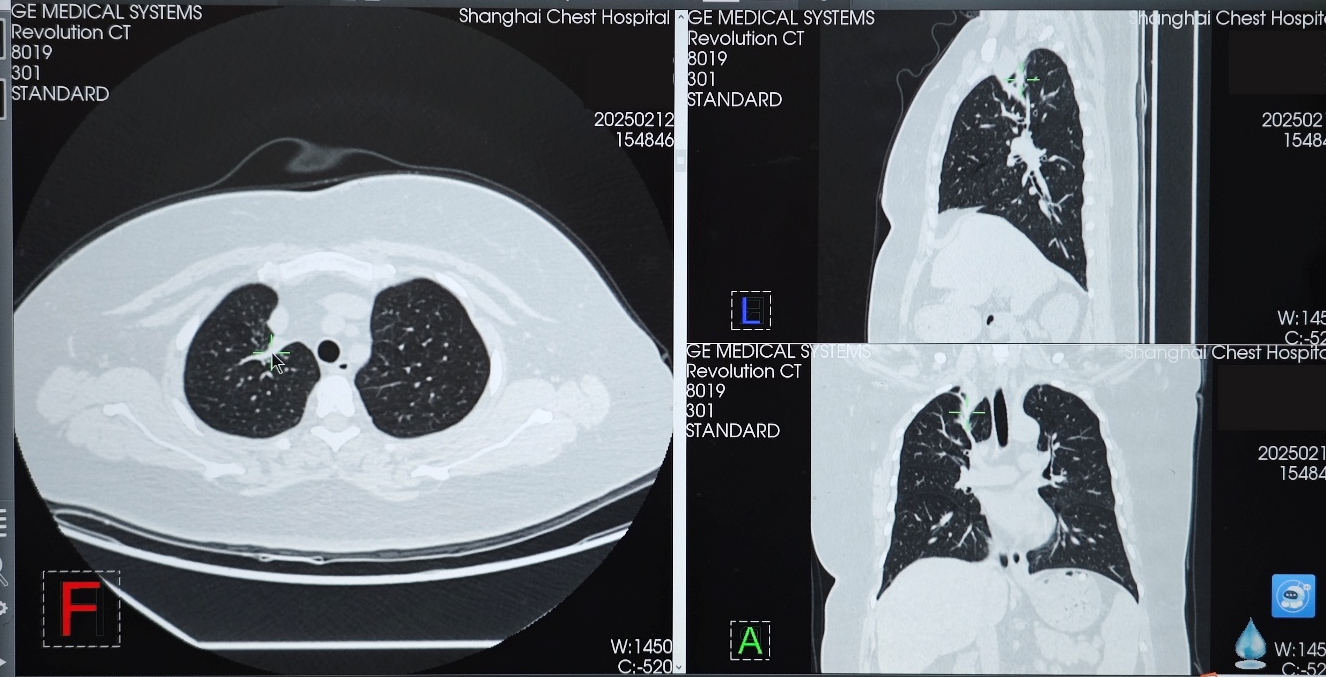

● 胸部CT(2021年6月11日):右肺上叶实性肿块影,大小约34×33mm,考虑肺癌;右肺门及纵隔淋巴结肿大。两肺多发微小结节。

2023年10月24日复查胸部CT,示右肺上叶实性肿块影,大小约37×15mm,与2023年8月25日CT相比病灶增大,评估为靶向治疗耐药导致疾病进展(PD)。

在变更骨保护药物方案前,患者免疫联合治疗达到并维持SD状态约10个月,在使用培美曲塞+PD-1+抗血管药物+地舒单抗后,患者肿瘤再次开始缩小,2025年2月复查胸部CT时,右肺上叶病灶缩小至24×11mm,达到PR。2025年8月复查胸部CT时,右肺上叶病灶进一步缩小至22×6mm,最佳疗效PR